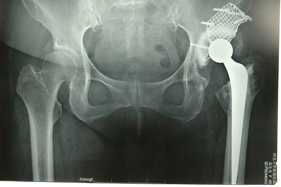

Department of Adult Joint Reconstructive Surgery

rivision total hip replacement for dislocation and severe bone defect

(post-op)rivision total hip replacement for dislocation and severe bone defect

anterior-posterior view of left hip

anterior-posterior view of bilateral hips